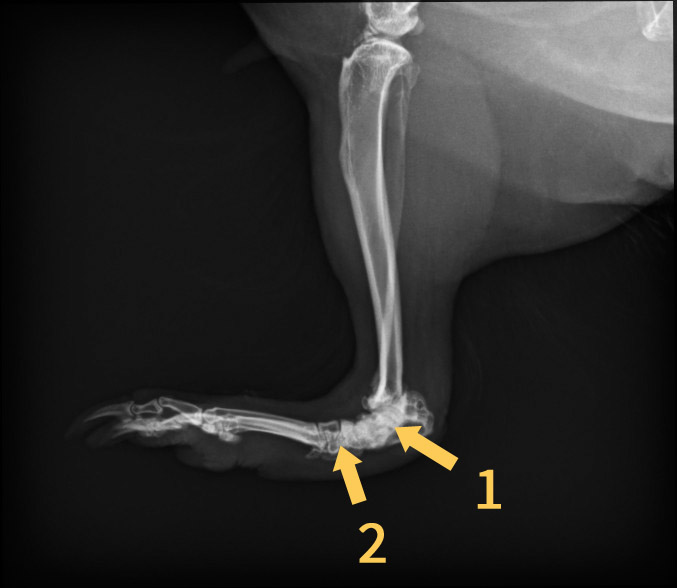

• Ich habe heute von Helga die Röntgenbilder bekommen. Zudem habe ich eine Physiotherapeutin gefunden. die sich an Schweinchen mal ausprobieren würde. Helga kommt mittlerweile mutig her und nimmt Futter gerne. Nur die Medis muss ich noch reinschmuggeln. Sie läuft auch deutlich besser und mehr. Ihr Schilddrüsenwert war tatsächlich mit 0,9 unter dem Grenzwert von 1,1 (Ich weiß die Einheit leider nicht). Da das ja alles nicht so eindeutig ist fordert die Tierärztin nochmal einen Wert nach und wir kontrollieren in 4-6 Wochen und stellen sie dann bei Bedarf ein.

Die Röntgenaufnahmen würde ich gerne besser verstehen:

Auf der zweitletzten Aufnahme ist das Sprungelenk m.E. klar als das zu sehen, was bei uns Menschen im Bereich der Ferse wäre. Etwas weiter links davon das dunklere ist dann vermutlich der Mittelfußknochen?

Du hattest geschrieben, dass Ihr Sprunggelenk stark geschädigt ist. Aber sieht es auf dem letzten Bild nicht so aus, als sei auch der Mittelfußknochen kaputt?

• Ich habe in den Bildern 1 und 2 markiert. Dabei vermute ich, dass 1 das Sprungelenk ist und 2 der Mittelfußknochen. Falls das richtig sein sollte, sieht der doch auf dem 2. Bild auch nicht normal aus?

Wie gesagt, ich verstehe kaum etwas davon und kann falsch liegen. Mach Dir daher bitte keine unnötigen Sorgen.

Den hatte ich glatt übersehen. Ich könnte mir vorstellen, dass die Ärztin mit Sprunggelenk den Teil eingeschlossen hat, da der gesamte Bereich falsch ausgebildet ist. Weißt du, was ich meine? Ich habe leider gerade unsere anderen Röntgenbilder von Füßchen nicht zur Hand um das zu vergleichen.